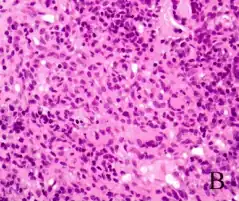

| Granulomatosis with polyangiitis | |

Systemic vasculitides are a group of heterogeneous diseases that share the etiology in terms of inflammation of the blood vessels (vasculitis) – more specifically the arterioles – with systemic envolvement. Some examples of this group include granulomatosis with polyangiitis, polyarteritis nodosa, Behçet's disease, and HSP.[1][2][3][4][5]